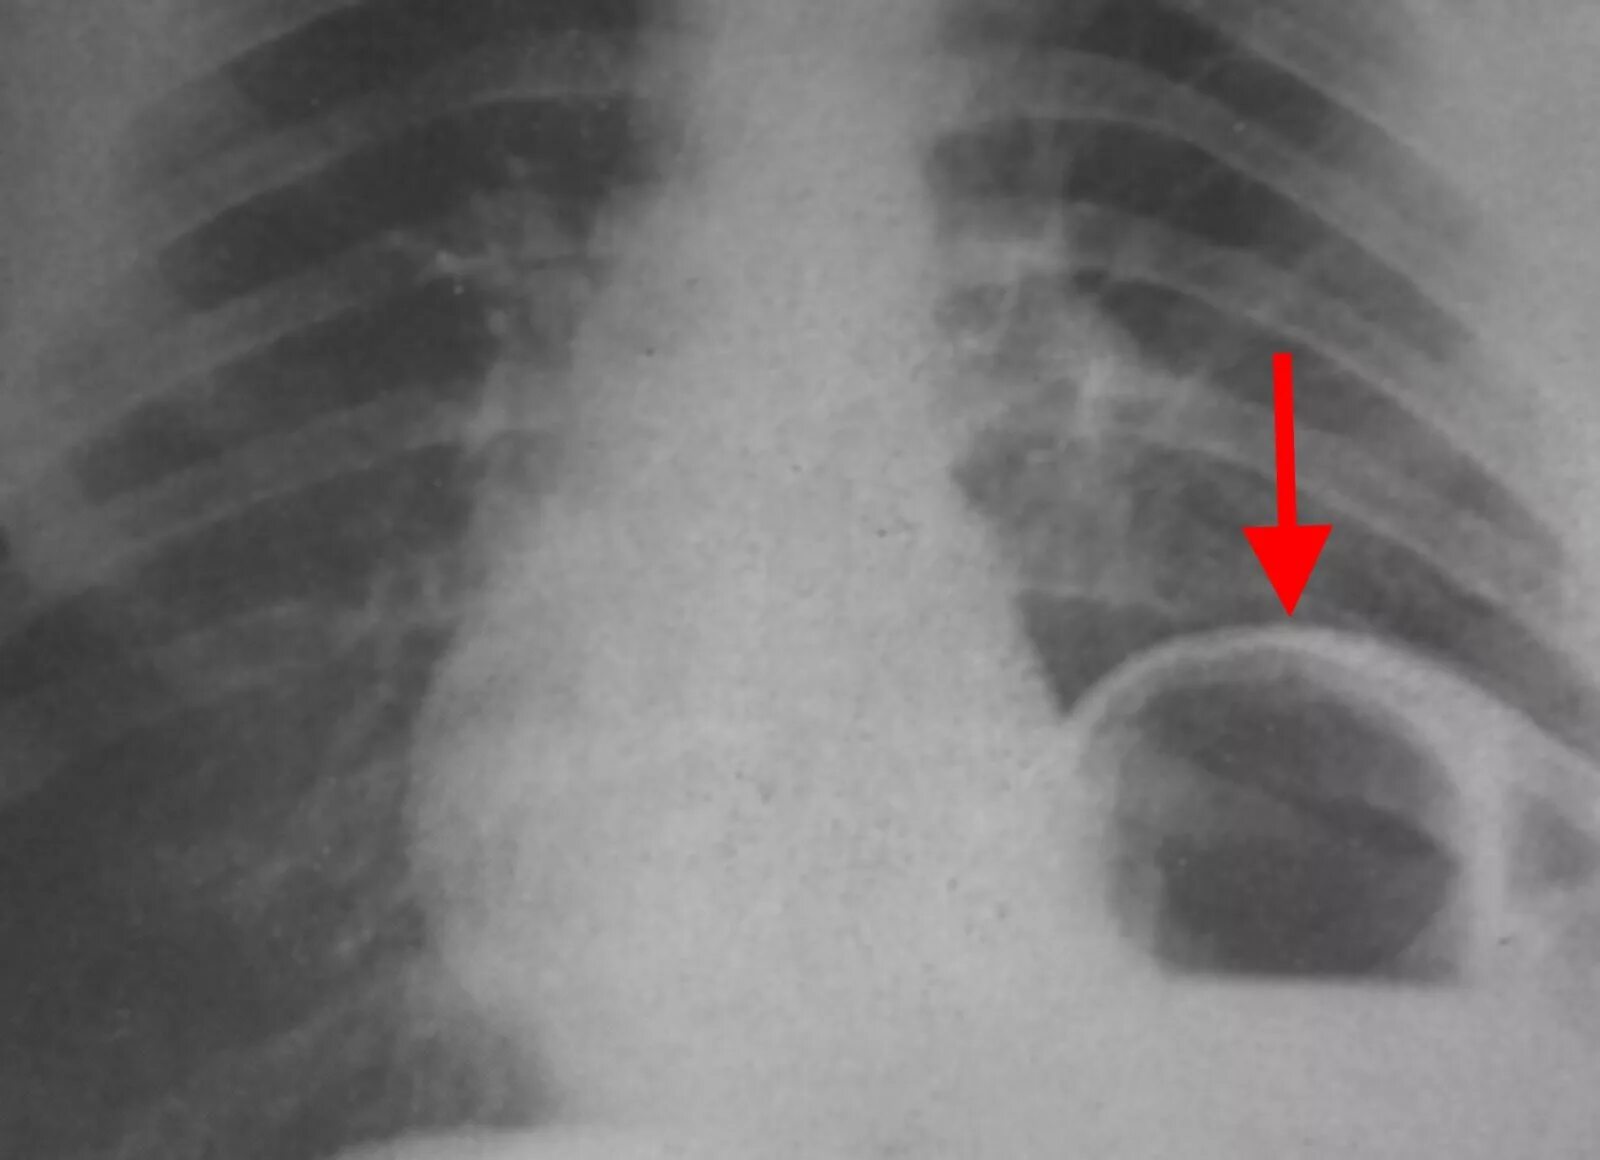

Уплотнение диафрагмы